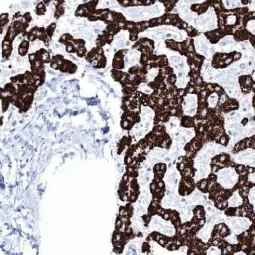

With this in mind, GeneTex is proud to introduce its HistoMAX product line that consists of antibodies specifically vetted for IHC. All of these reagents were extensively evaluated for IHC utilizing formalin-fixed normal and cancer tissue microarrays to guarantee specificity and best-in-class performance. Only antibodies that have passed these stringent performance criteria for IHC will be added to the HistoMAX portfolio.![]()